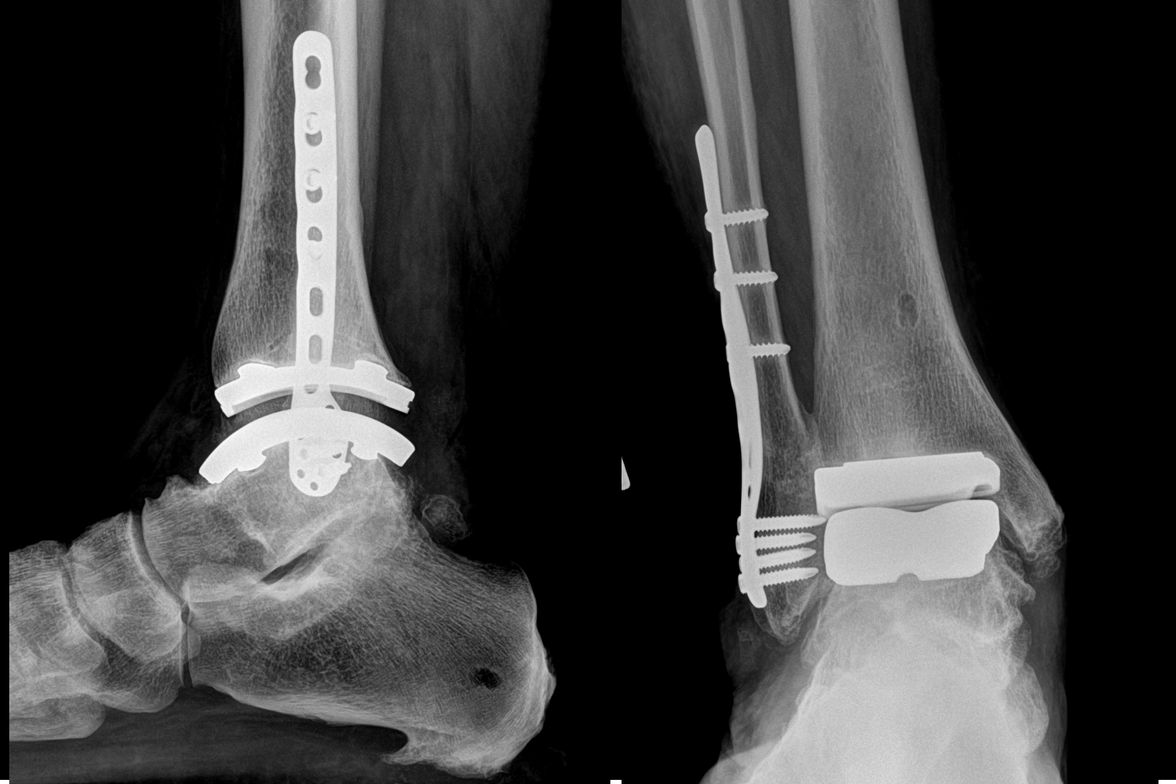

Total ankle replacement is a surgery that removes the damaged part of your arthritic ankle joint and replaces it with a metal and plastic implant. The goal is to:

ankle replacement xray.png